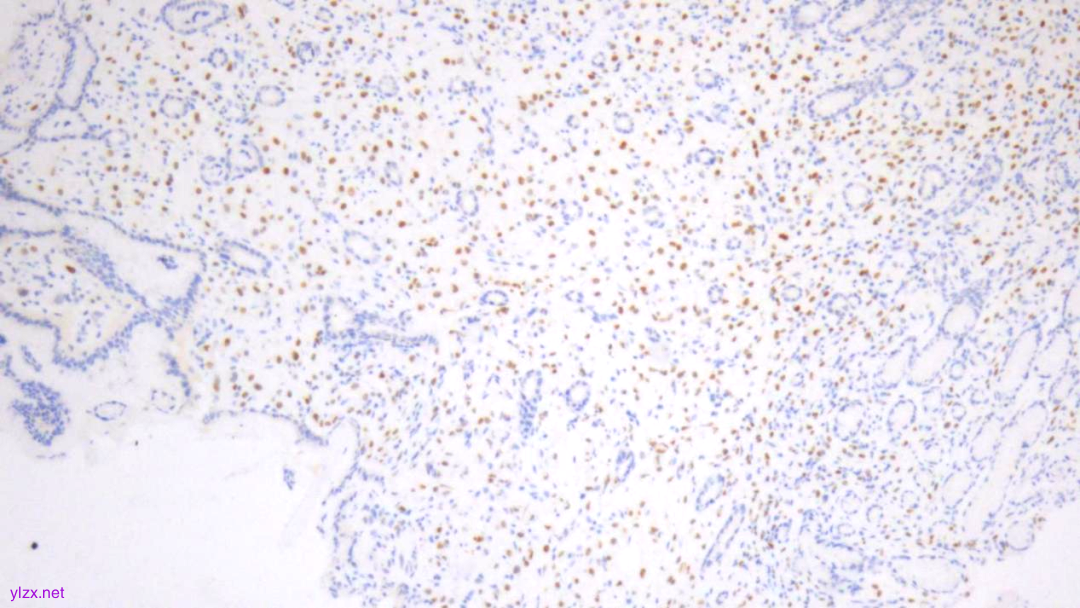

IHC结果:

P120(浆+),P16(灶+),P53(野生型表达),Her2(1+),CK7、GATA3、GCDFP-15、CK-H均(+),ER、PR、E-Cadherin、CK20均(-),Ki67(约5%+)

ER(-)

PR(-)

E-Cadherin(-)

Ki-67(散在+)